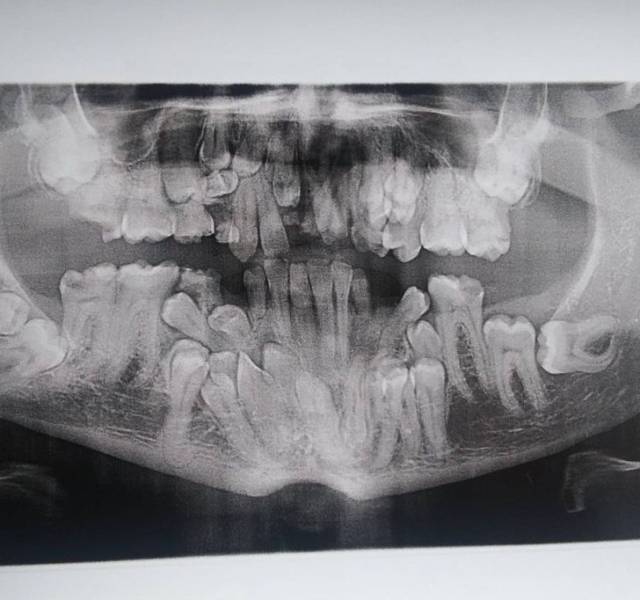

“I have a rare disorder called cleidocranial dysostosis. Got my first dental X-ray today and I have a lot of extra teeth.”